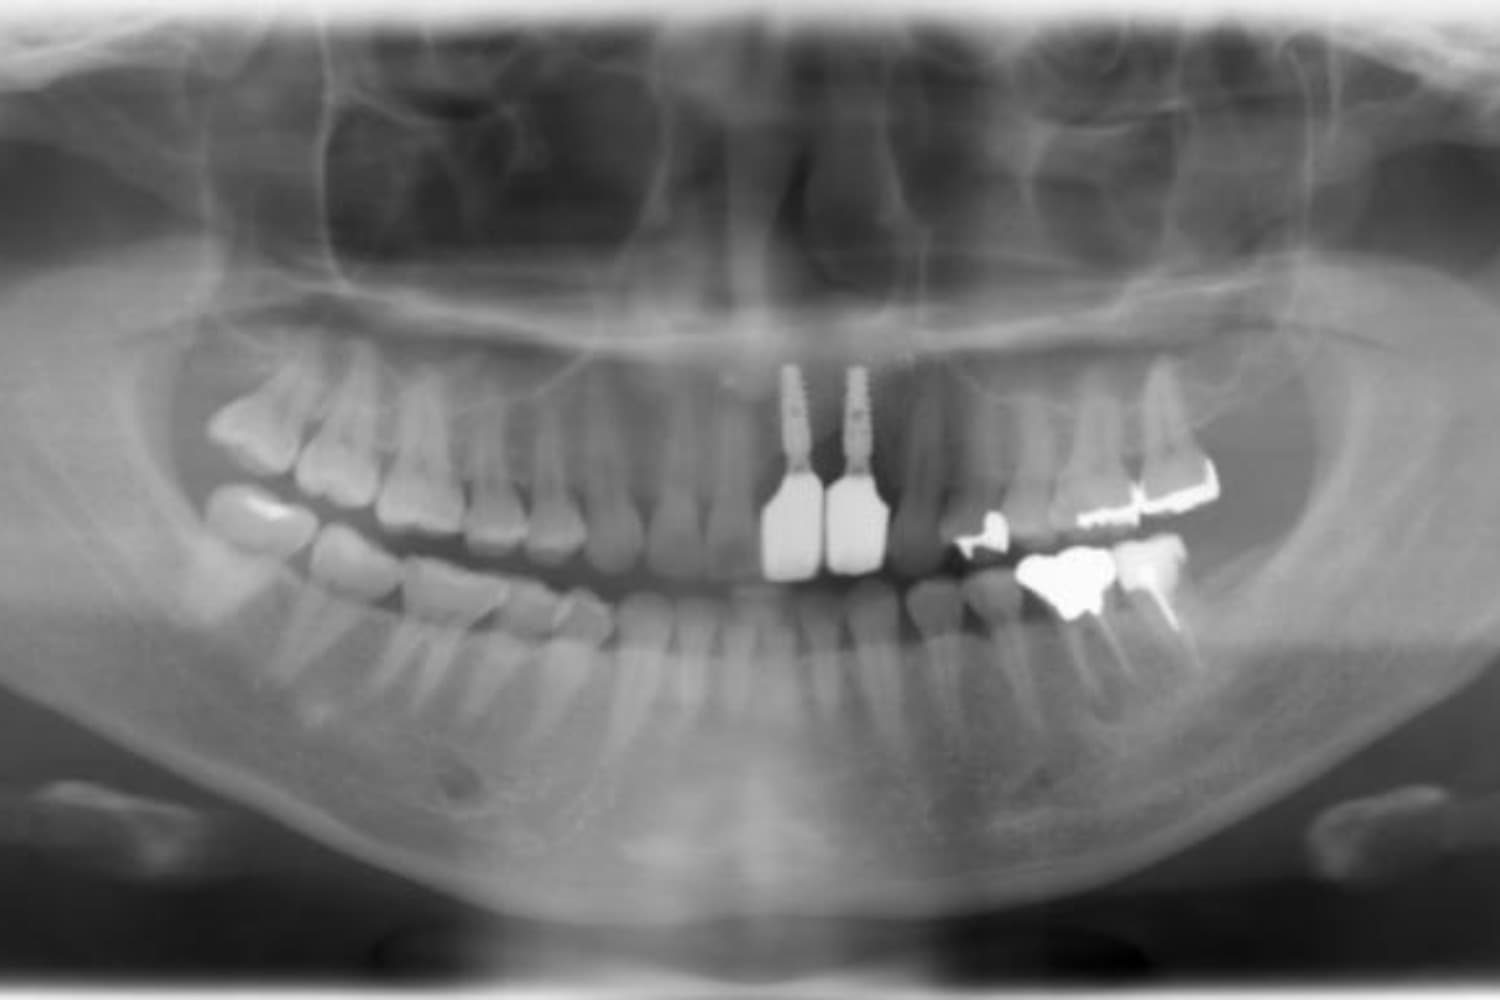

下顎大臼歯3本欠損症例

After

左下第一大臼歯は保存が困難な状態であったため抜歯をおこないました。あわせて、ご来院時から欠損していた右下第一・第二大臼歯も含め、欠損部の補綴方法についてご説明し、インプラント治療を選択されました。

年齢

60歳

性別

男性

主訴

左下の第一大臼歯は別の医院で治療中でしたが、治療が思うように進まず、加えて他の箇所にも痛みが続いたことから、当院にご相談いただきました。

治療期間

10ヵ月

費用

140万円

副作用・リスク

インプラント治療は外科的な処置を伴い、多少の腫れや痛みが出ることがあります。 多くの場合は鎮痛薬で和らげることができます。